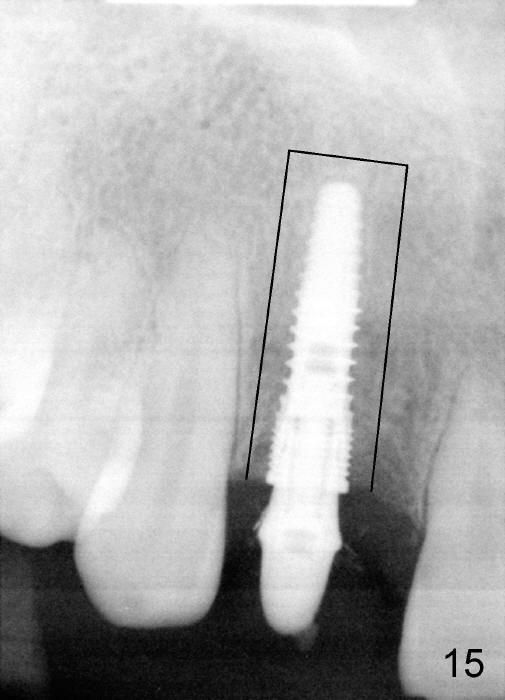

PA in Fig.15 is taken 1.5 months postop. It appears that there is enough space to make osteotomy around the implant (black outline) and move the segment coronally (Fig.16).